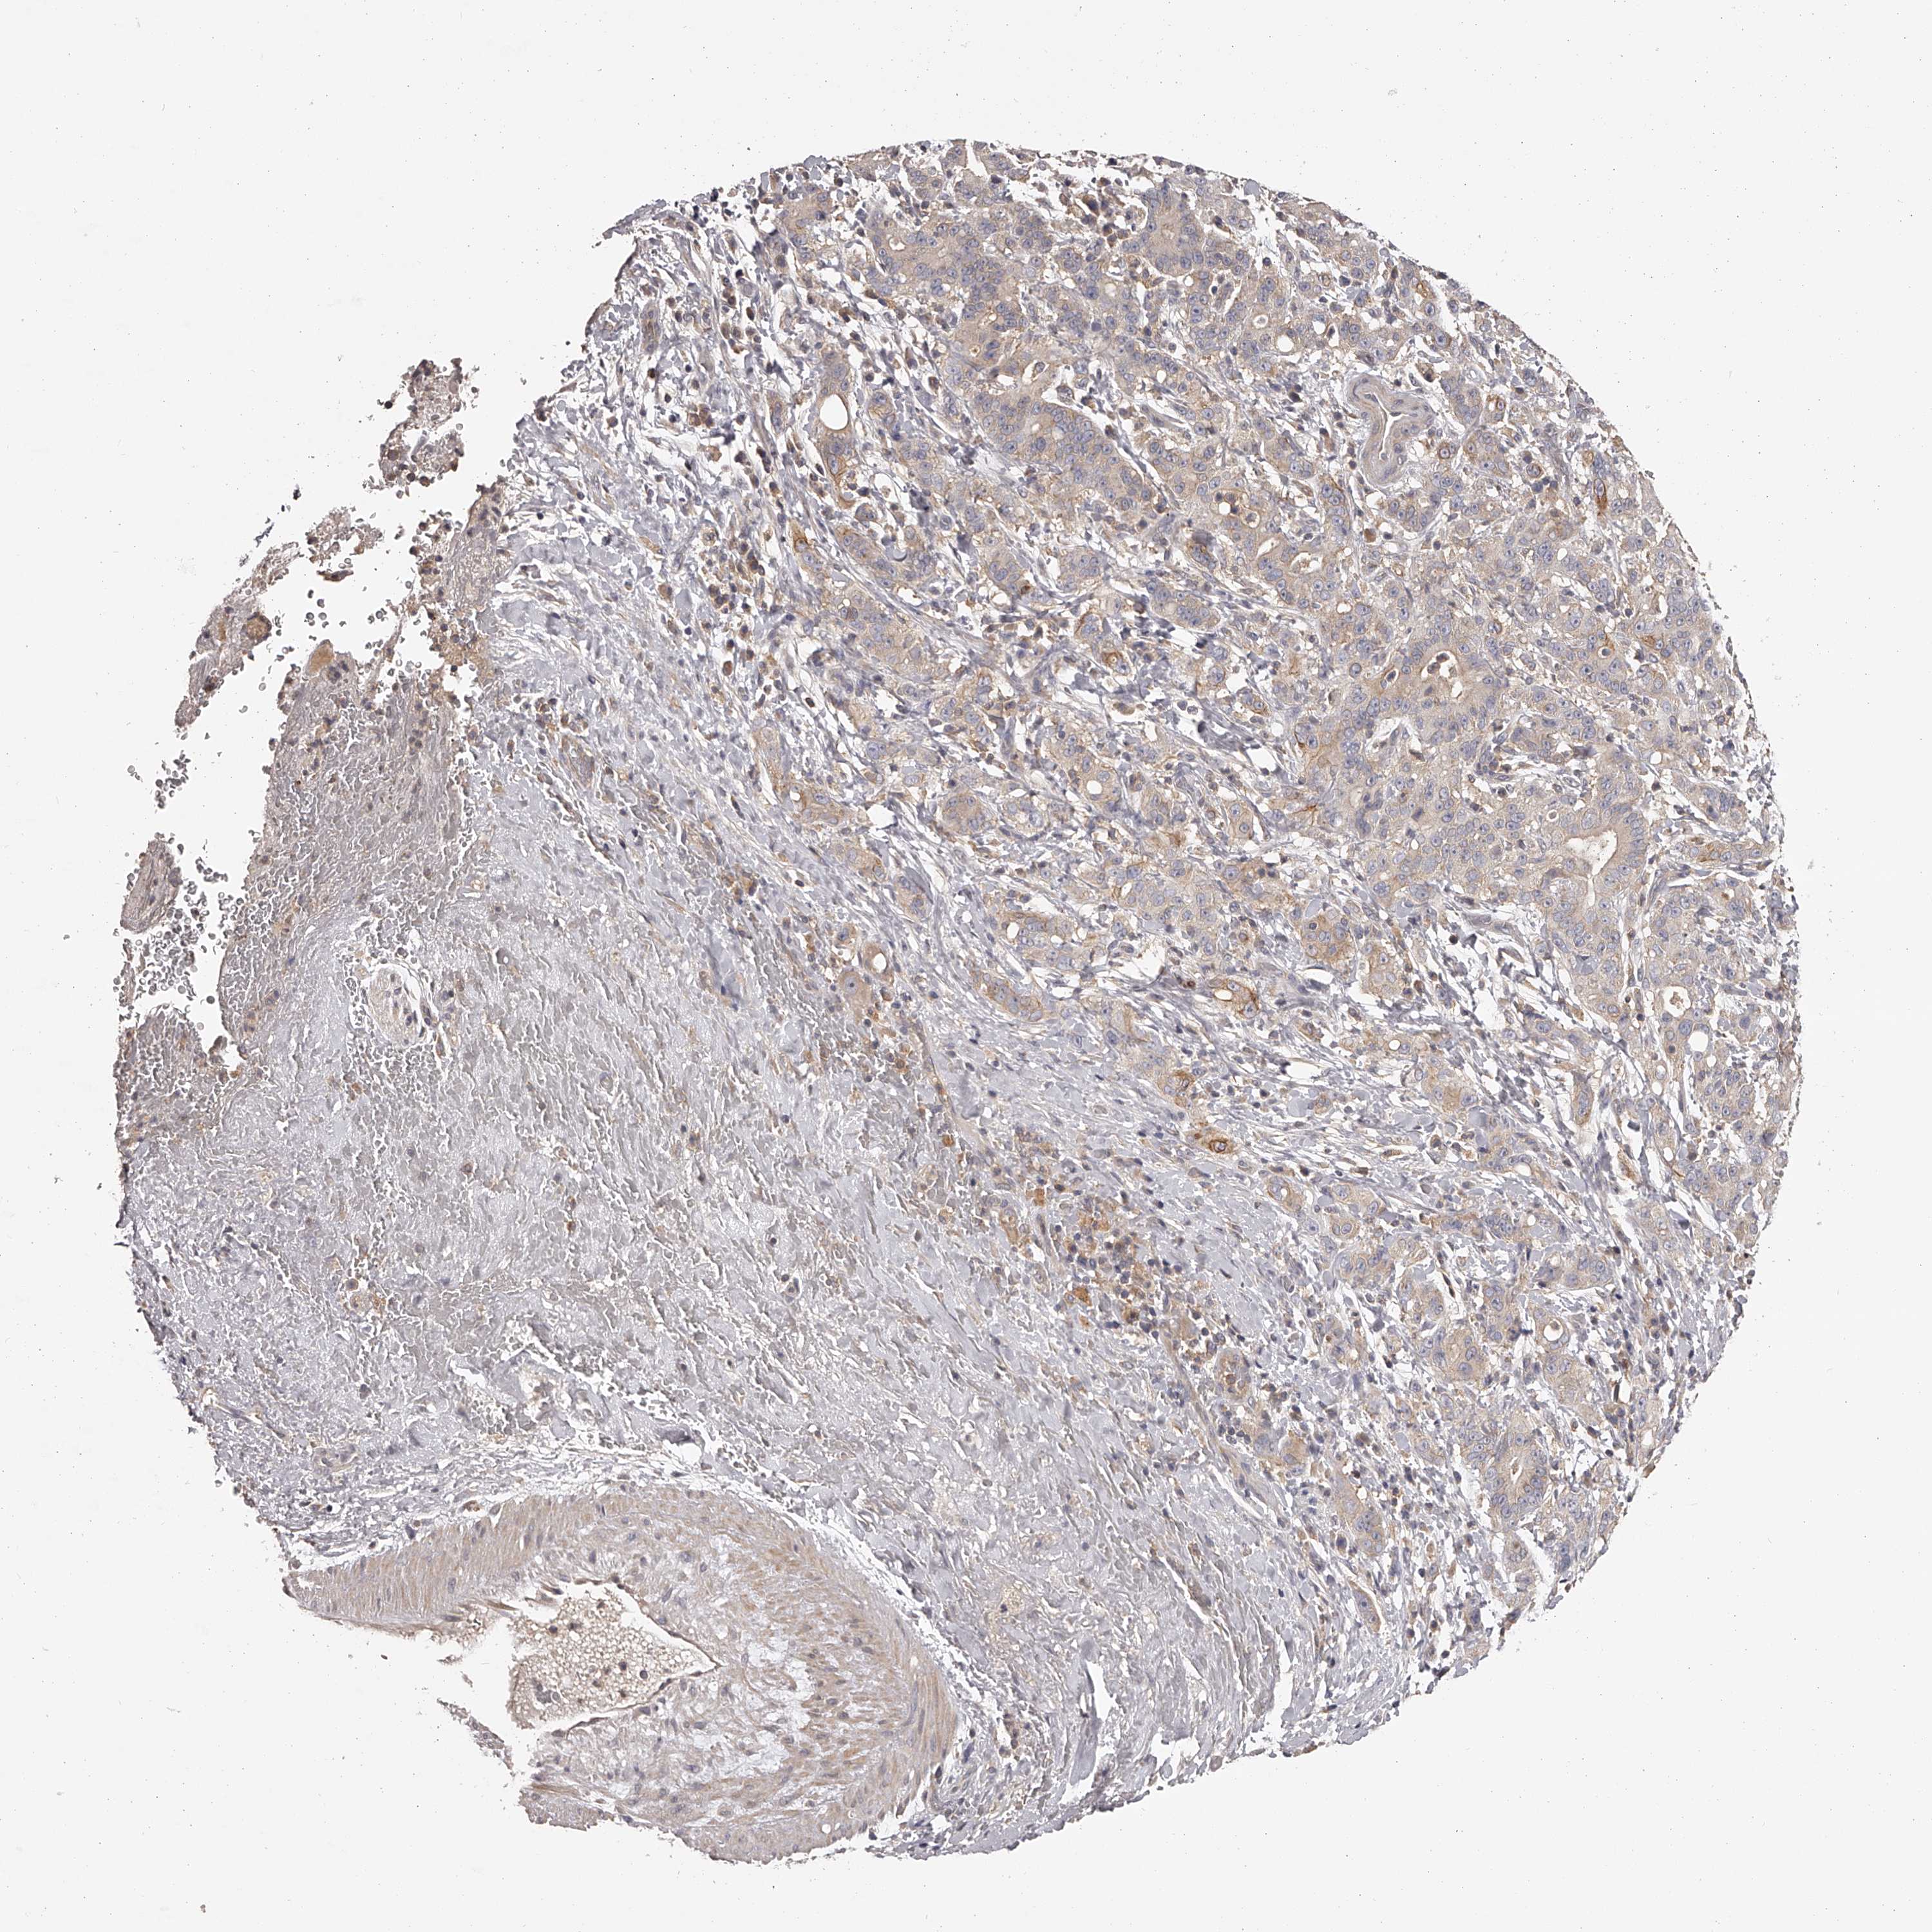

LIVER CANCER - Protein expressioni

A mouse-over function shows sample information and annotation data. Click on an image to view it in a full screen mode. Samples can be filtered based on level of antibody staining by selecting one or several of the following categories: high, medium, low and not detected. The assay and annotation is described here.

Note that samples used for immunohistochemistry by the Human Protein Atlas do not correspond to samples in the TCGA dataset.

Antibody stainingi

Antibody staining in the annotated cell types in the current human tissue is reported as not detected, low, medium, or high, based on conventional immunohistochemistry profiling in selected tissues. This score is based on the combination of the staining intensity and fraction of stained cells.

Each image is clickable and will lead to virtual microscopy that enables deeper exploration of all samples and also displays staining intensity scores, fraction scores and subcellular localization as well as patient and tissue information for each sample.

Antibody HPA026726

Antibody HPA026764

Antibody CAB010907

Staining

High

Medium

Low

Not detected

Intensity

Strong

Moderate

Weak

Negative

Quantity

>75%

75%-25%

<25%

None

Location

Nuclear

Cytoplasmic/membranous

Cytoplasmic/membranous,nuclear

Cholangiocarcinoma

Carcinoma, Hepatocellular, NOS